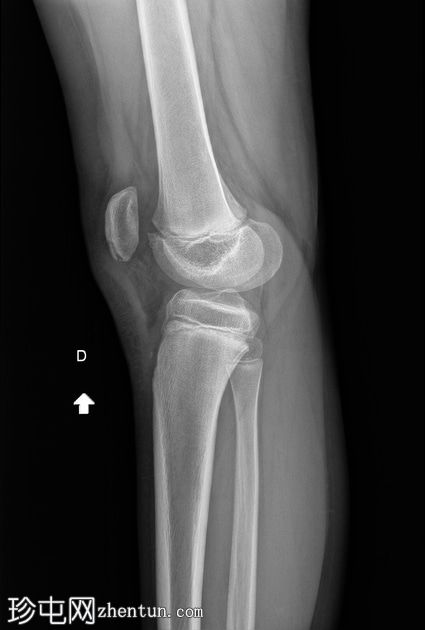

侧位 -

负重位

髌骨下极可见一小块薄骨碎片,伴有髌骨高位,Insall-Salvati比值为1.5(V.N. 0.8 - 1.2)。膝前可见软组织肿胀。左膝正常。